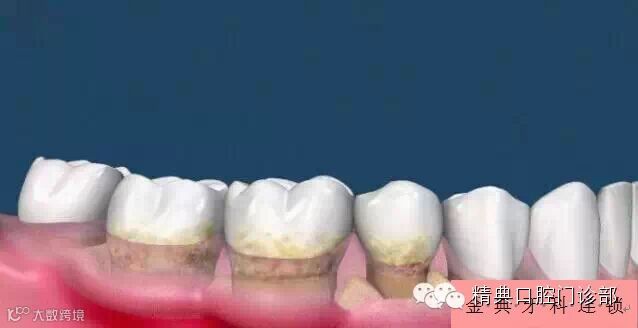

图片四、牙菌斑和牙结石没有被及时的清除,牙龈进一步的红肿,这是您会发现牙龈偶尔有出血。

图片五、此时在牙龈以下也同样存在着坚硬的牙结石。这些牙结石开始刺激牙槽骨,牙槽骨害怕了,向后退缩,导致牙根开始慢慢暴露出来。